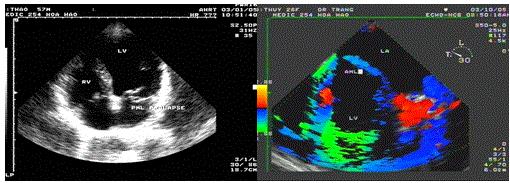

Mitral valve prolapse

Mitral valve prolapse (MVP) occurs in 2% of the general population.

The risk of thromboembolic complications in MVP occurs when significant thickening of mitral valve, accompanied by LA dilatation, atrial fibrillation [33].

There are 3 cases in our data, all cases are severe mitral regurgitation and LA dilation (Figures 21-23).

Figure 21. Prolapse of the PML, “TEE with TDI recorded by Le Huu Quynh Trang”

Figure 22. PML prolase due to chordae rupture; “LAX view made by Nguyen Tuan Vu

Figure 23. Apcal 4 C view show PML prolapse; 3D TTE performed by Nguyen Tuan Vu